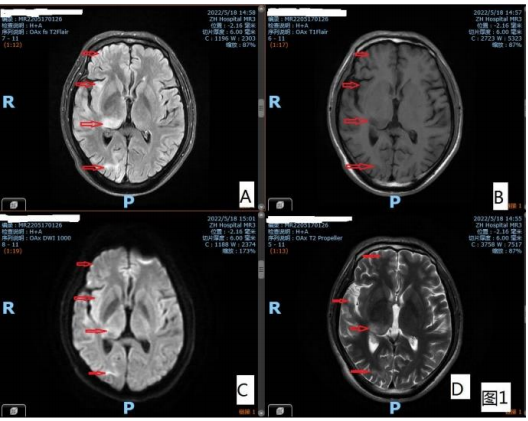

图 1 右侧外囊、颞叶、额叶、丘脑多发片状/斑片状 T1WI 稍低/低信号,T2WI 高信号,T2-Flair 高信号,DWI 稍高 信号影

颅脑 MRI:右侧顶叶、双侧颞叶、双侧枕叶、右侧岛 叶、右侧外囊、右侧丘脑、左侧海马、中脑、脑桥背侧可 见多发斑片状、片状 T1WI 低信号、T2WI 高信号、DWI 稍高信号,如图 1、图 2。